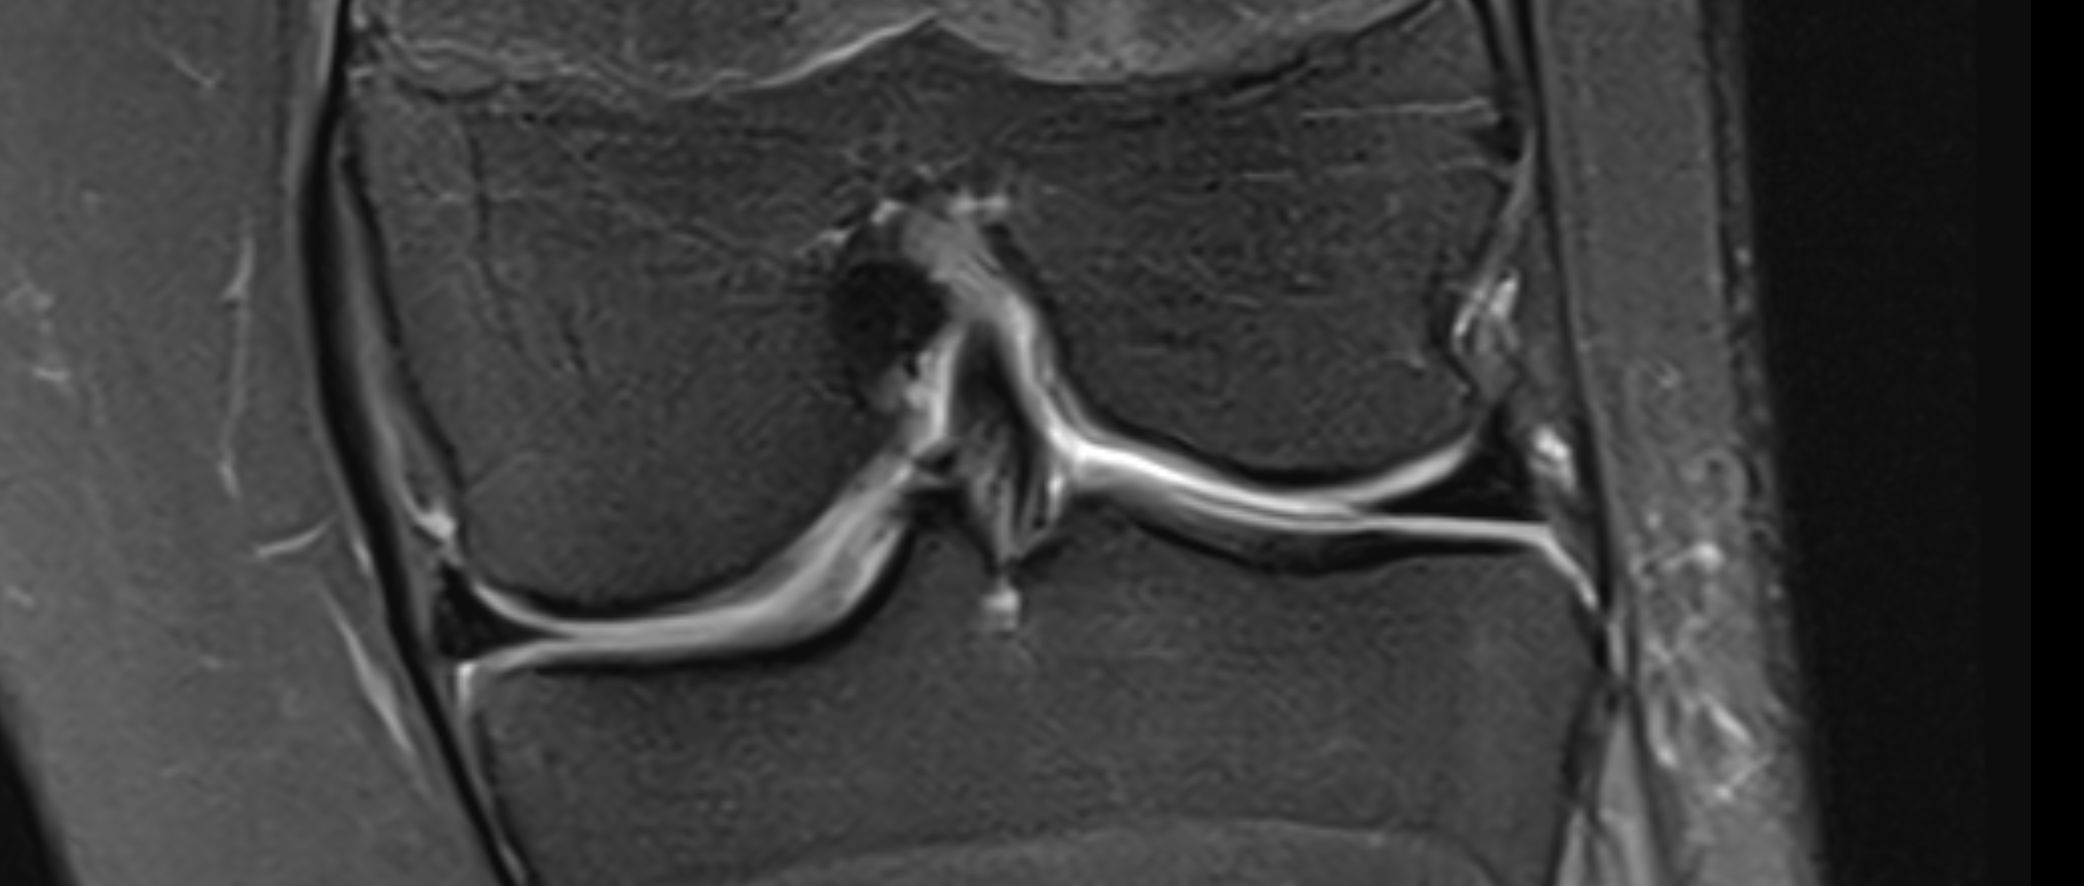

The Double PCL Sign

View: Sagittal (Midline)

Double PCL Sign

What the marker shows: The native Posterior Cruciate Ligament (PCL) is the top dark band. The red marker highlights the second band resting directly beneath it.

This lower band is the torn inner rim of the meniscus that has migrated into the center of the knee joint.